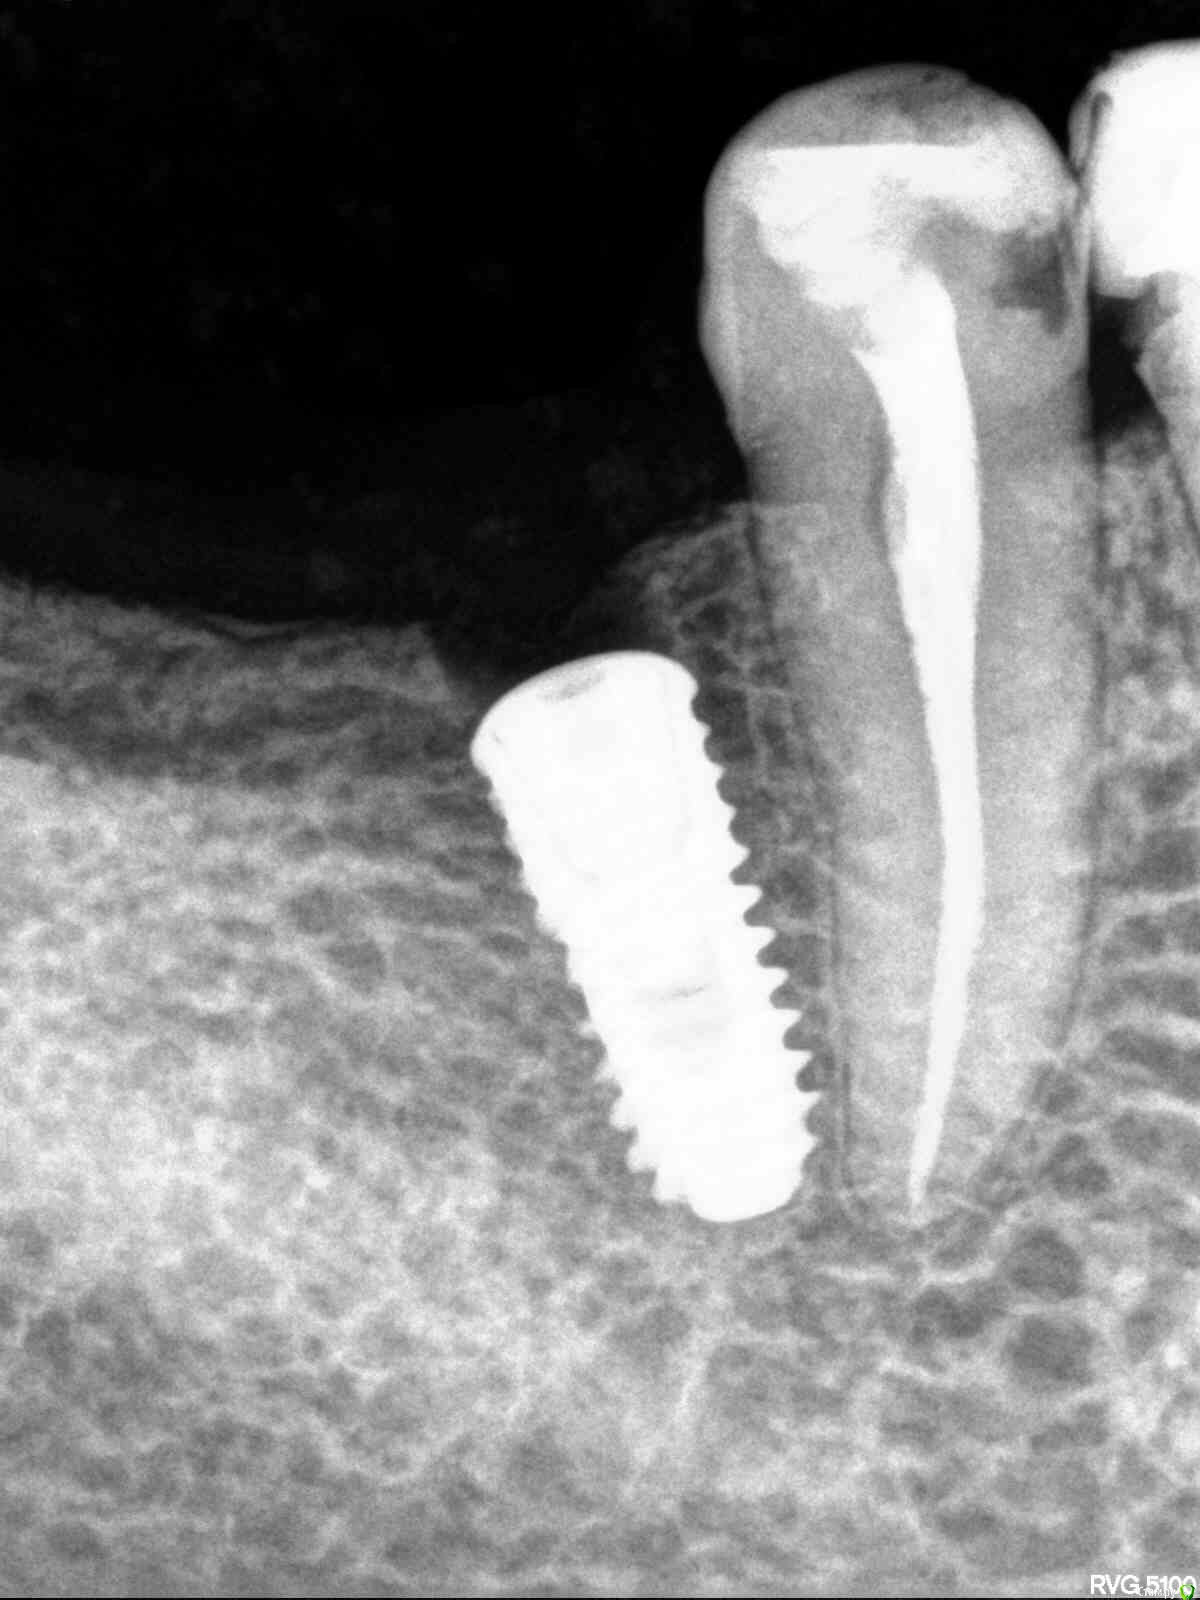

Кариес+ Опубликовано 11 марта, 2016 Поделиться Опубликовано 11 марта, 2016 (изменено) Чем чревато такое положение имплантата? Насколько правдив факт , что между коронкой одиночно стоящего импланта при концевом деффекте и зубом по контакту образуется щель в дальнейшем? Изменено 11 марта, 2016 пользователем Кариес+ Ссылка на комментарий

Кариес+ Опубликовано 11 марта, 2016 Автор Поделиться Опубликовано 11 марта, 2016 (изменено) И можно ли заглублять имплантат если у вершины к примеру толщина гребня 5мм , а на 2-3мм глубже 6-7мм? (Диаметр импл 4мм) Изменено 11 марта, 2016 пользователем Кариес+ Ссылка на комментарий

carloss Опубликовано 11 марта, 2016 Поделиться Опубликовано 11 марта, 2016 всё там хорошо, не переживайте .. чтобы не было щели, или минимально, побольше походить с времянкой.. или коронку на своем можете сделать через год, тем самым прикрыв щель имплантат заглублять нужно в таких случаях 3 Ссылка на комментарий